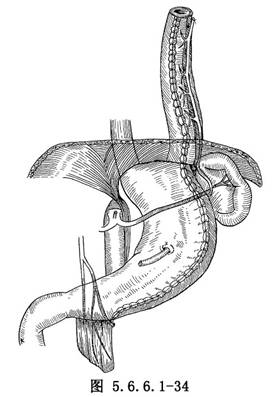

8.3 3.倒置胃管食管重建术

利用胃大弯制成长管用以重建食管。患者取仰卧位,腹部正中切口及左颈部切口或侧卧位左侧胸腹联合切口,游离大网膜,在幽门附近结扎切断胃网膜右血管,保留胃网膜左血管。在距幽门5cm处由垂直方向切开胃大弯约3cm,由此切口靠近大弯侧置入一根10cm长、直径为2cm的硬质胶管,沿此胶管切开胃前、后壁直至肝底,用细丝线间断缝合两层(图5.6.6.1-33)。如此制成的胃管可逆转向上提至颈部与食管作吻合(图5.6.6.1-34)。此术式的优点是能保留大部分胃在正常位置,缺点为缝合线过多,手术费时间,术后发生吻合口瘘及缝线边缘瘘的机会较多,近年已较少应用。